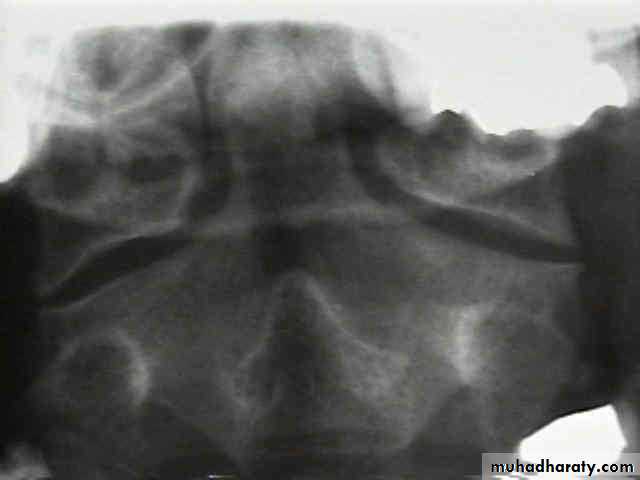

DIAGNOSISX RAY

Anterio posterior X ray radiograph.lateral radiographs with the head in flexion and extension may revealinstability that is not shown in the routine lateral film.

oblique views

at 45° are especially helpful

a special projection

through the open mouth.